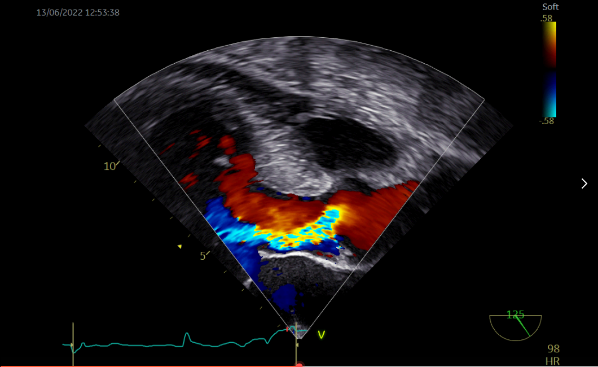

TEE显示瓣膜形态良好,无瓣周漏